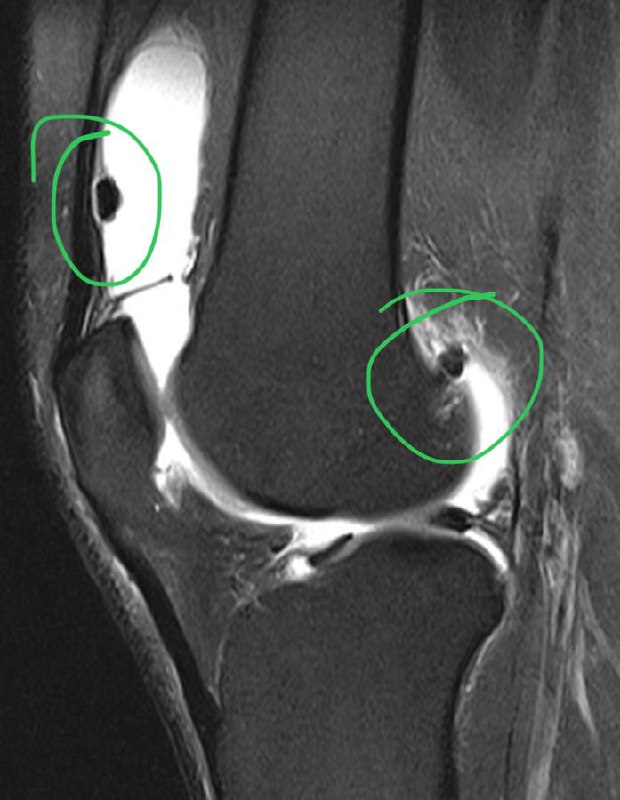

Подборка с рутины. Что видел за последние несколько дней.

Свободные костно-хрящевые внутрисуставные тела в коленном суставе.

Разрыв передней крестообразной связки. Угол между ней и крышей межмыщелковой ямки открыт не вперед, а назад.